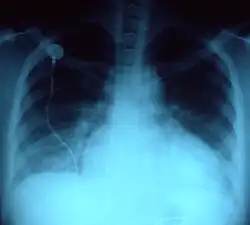

- No tipo longilíneo, indivíduos altos, magros, com uma distância púbis-pé superior à distância púbis-vértice da cabeça, tórax estreito, ombros estreitos, o coração adopta uma posição mais vertical tendo na radiografia torácica o aspeto chamado de "coração em gota". A ponta cardíaca desce abaixo do 5º espaço intercostal, mais central que a linha médio-clavicular e o impulso apical é por vezes sentido próximo do apêndice xifoide esternal.

- No morfotipo brevilíneo, indivíduos com o tórax largo, uma distância púbis-pé menor que a distância púbis-vértice, muitas vezes com excesso de peso e um diafragma elevado, o coração está numa posição mais horizontal. O impulso apical é desviado para acima do 4º espaço intercostal e para fora da linha médio-clavicular, na linha axilar anterior e mesmo por vezes na linha axilar média. Numa radiografia do tórax o coração aparece "deitado" sobre o diafragma dando um falso aspecto de dilatação cardíaca porque o índice cardiotorácico (sinal radiológico: razão entre o diâmetro do coração e o diâmetro torácico) está aumentado.[2]

- As doenças pulmonares alteram a posição do coração.[4]

- O enfisema pulmonar bilateral (se for simétrico) vai originar um reposicionamento cardíaco muito semelhante ao que aparece no indivíduo longilíneo.

- um pneumotórax vai desviar o coração e o choque da ponta para o lado contralateral.

- Na cardiomegalia global o choque da ponta está desviado para a esquerda por vezes a nível da linha axilar média.

- A patologia óssea da coluna ou do tórax provoca um reposicionamento cardíaco com desvio da ponta cardíaca e da localização do impulso apical, dependendo da patologia e da gravidade.